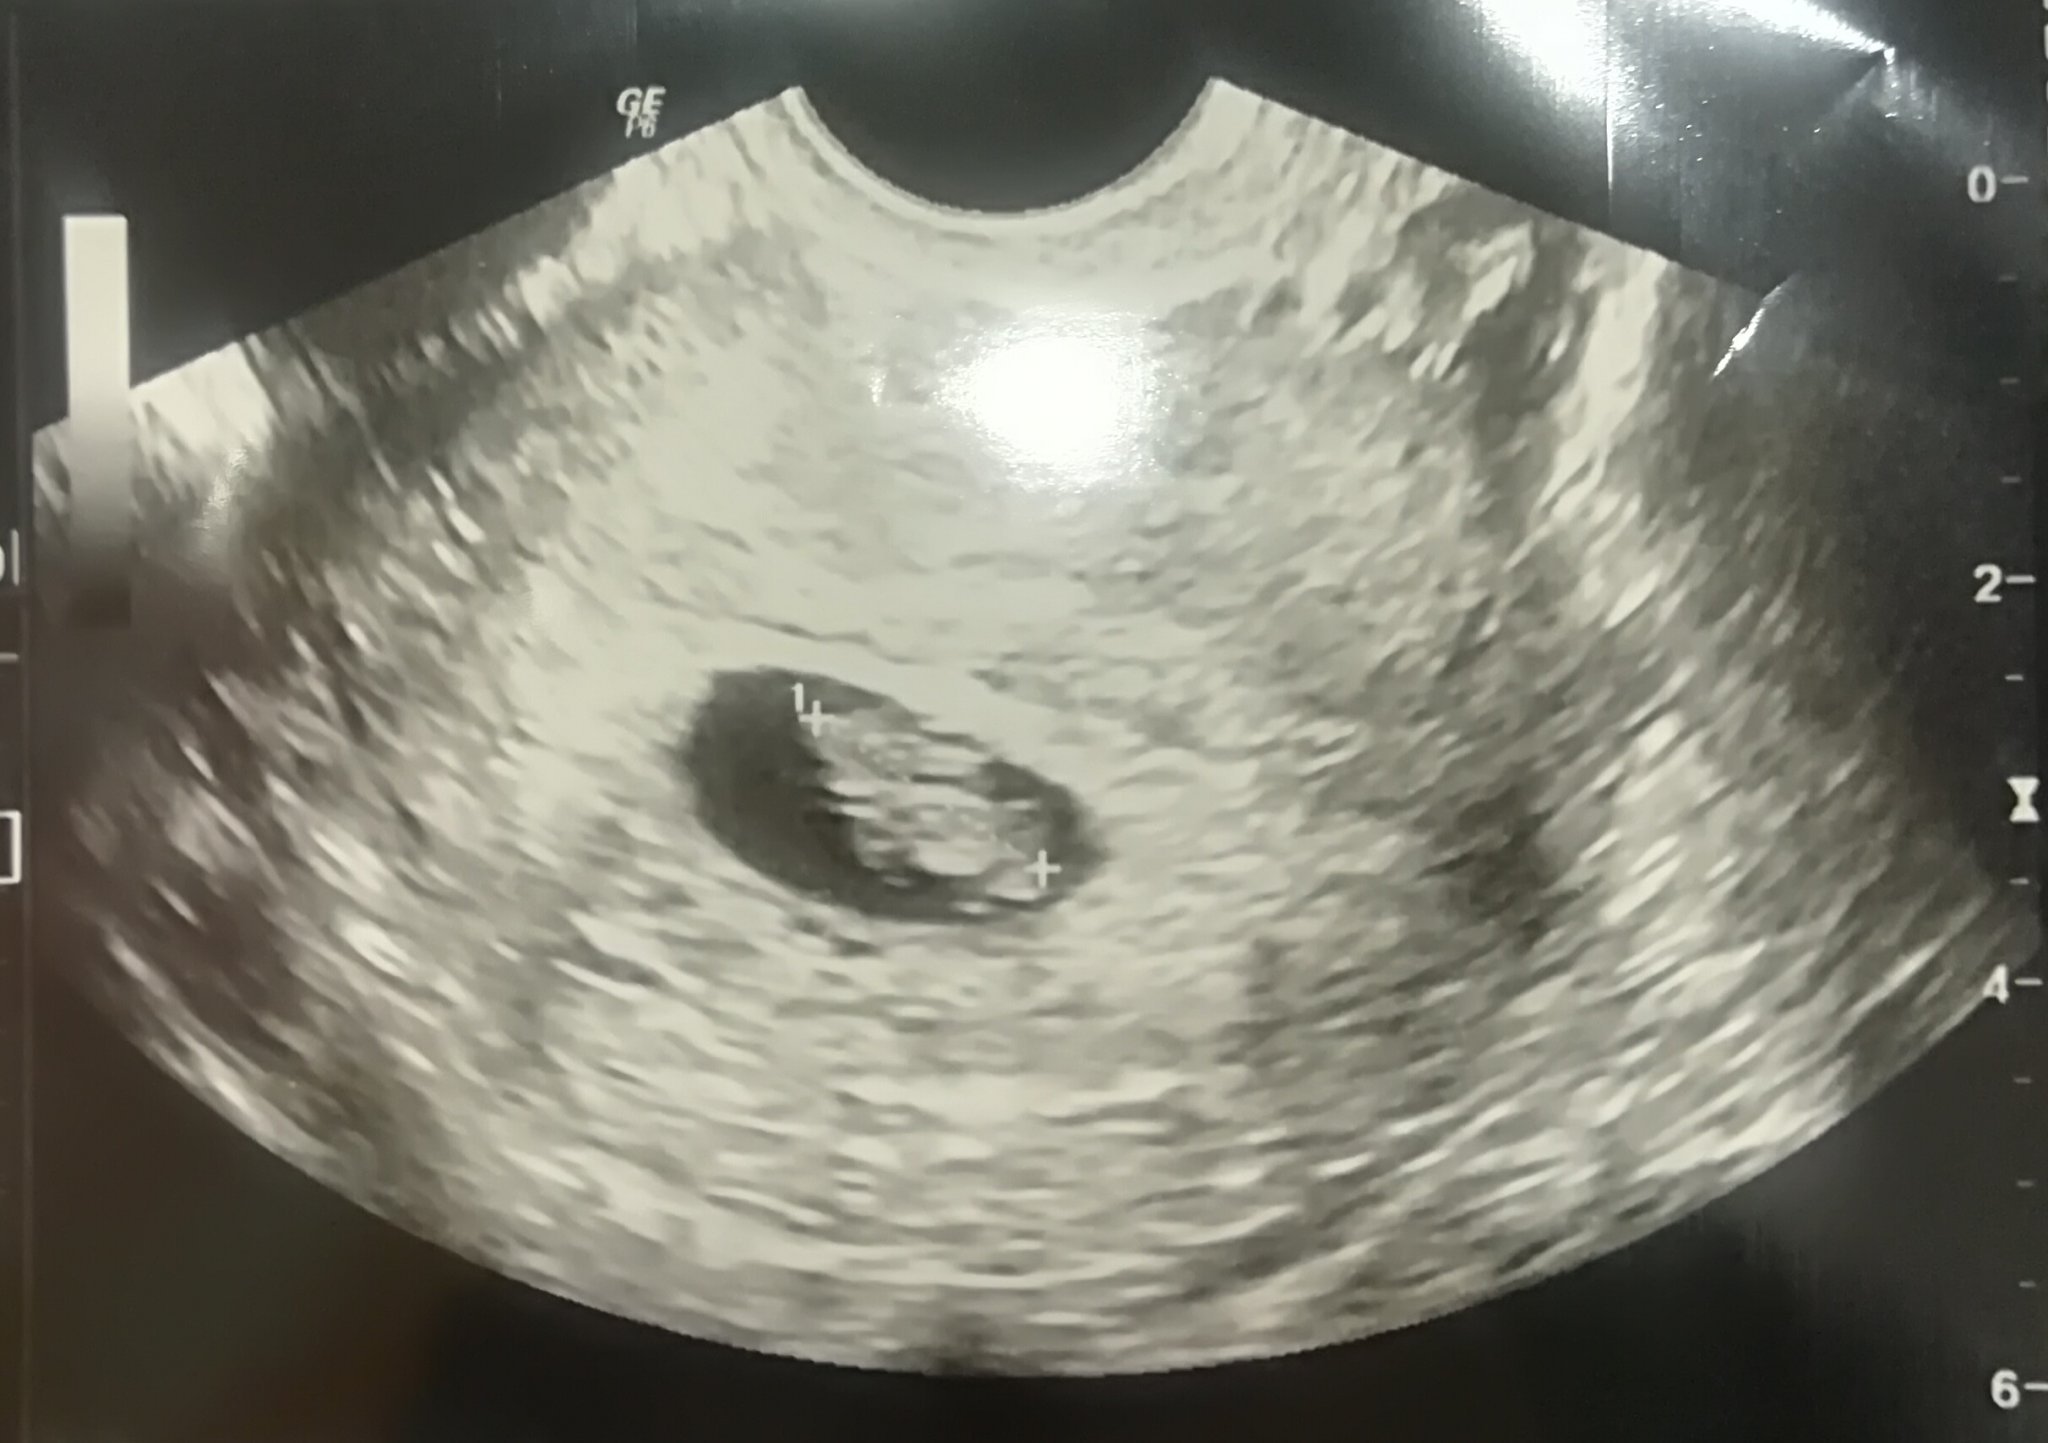

Кога може да се види нещо при коремна ехография?